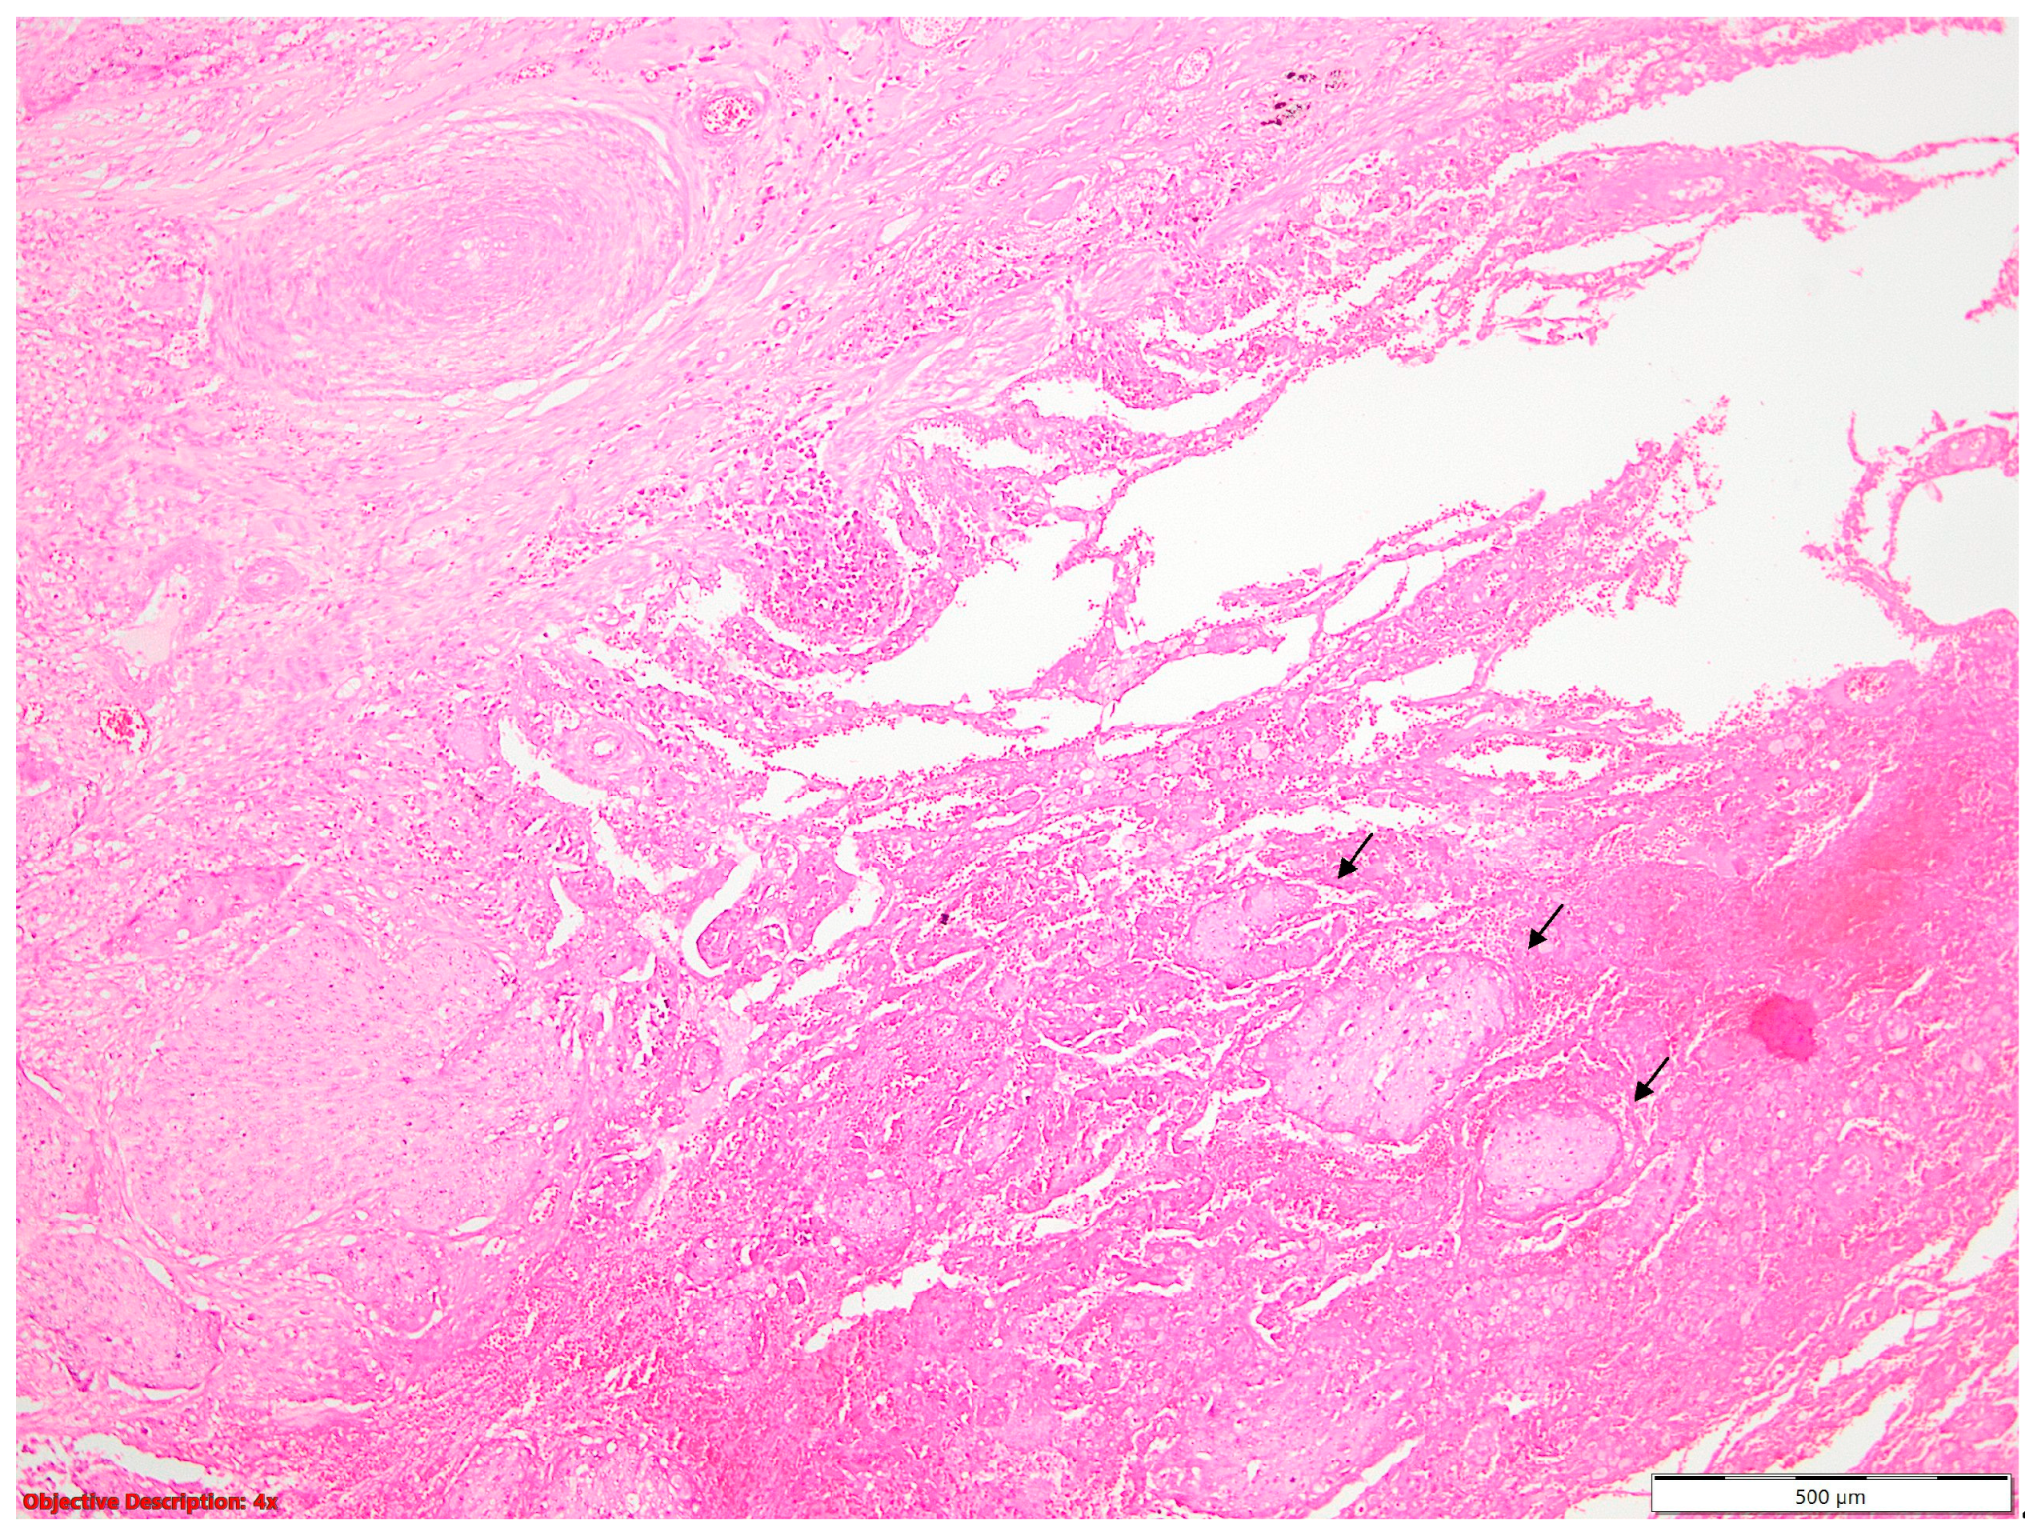

The Kaplan–Meier survival analysis was conducted on the entire cohort (N = 99 patients), of which 60% were men. The median age of the patients was 63 years old. Figure 3 and Table 1 depict the overall survival outcomes revealing a median survival of 36 months and a mortality rate of 65.65%.

Figure 3. Overall survival Graph.